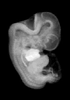

Human Embryo

Carnegie Stage 18 (44 post-ovulatory days)

Most embryos at stage 18 are approximately 44 postovulatory days old and measure 13-17 mm in length. Distinguishing criteria for this stage include cervical and lumbar flexures, distinct notching in the hand plate, the first appearance of the elbow, eyelid folds may appear in more advanced specimens, and auricular hillocks begin to form distinct parts of the external ear.

MRI Slice Selector